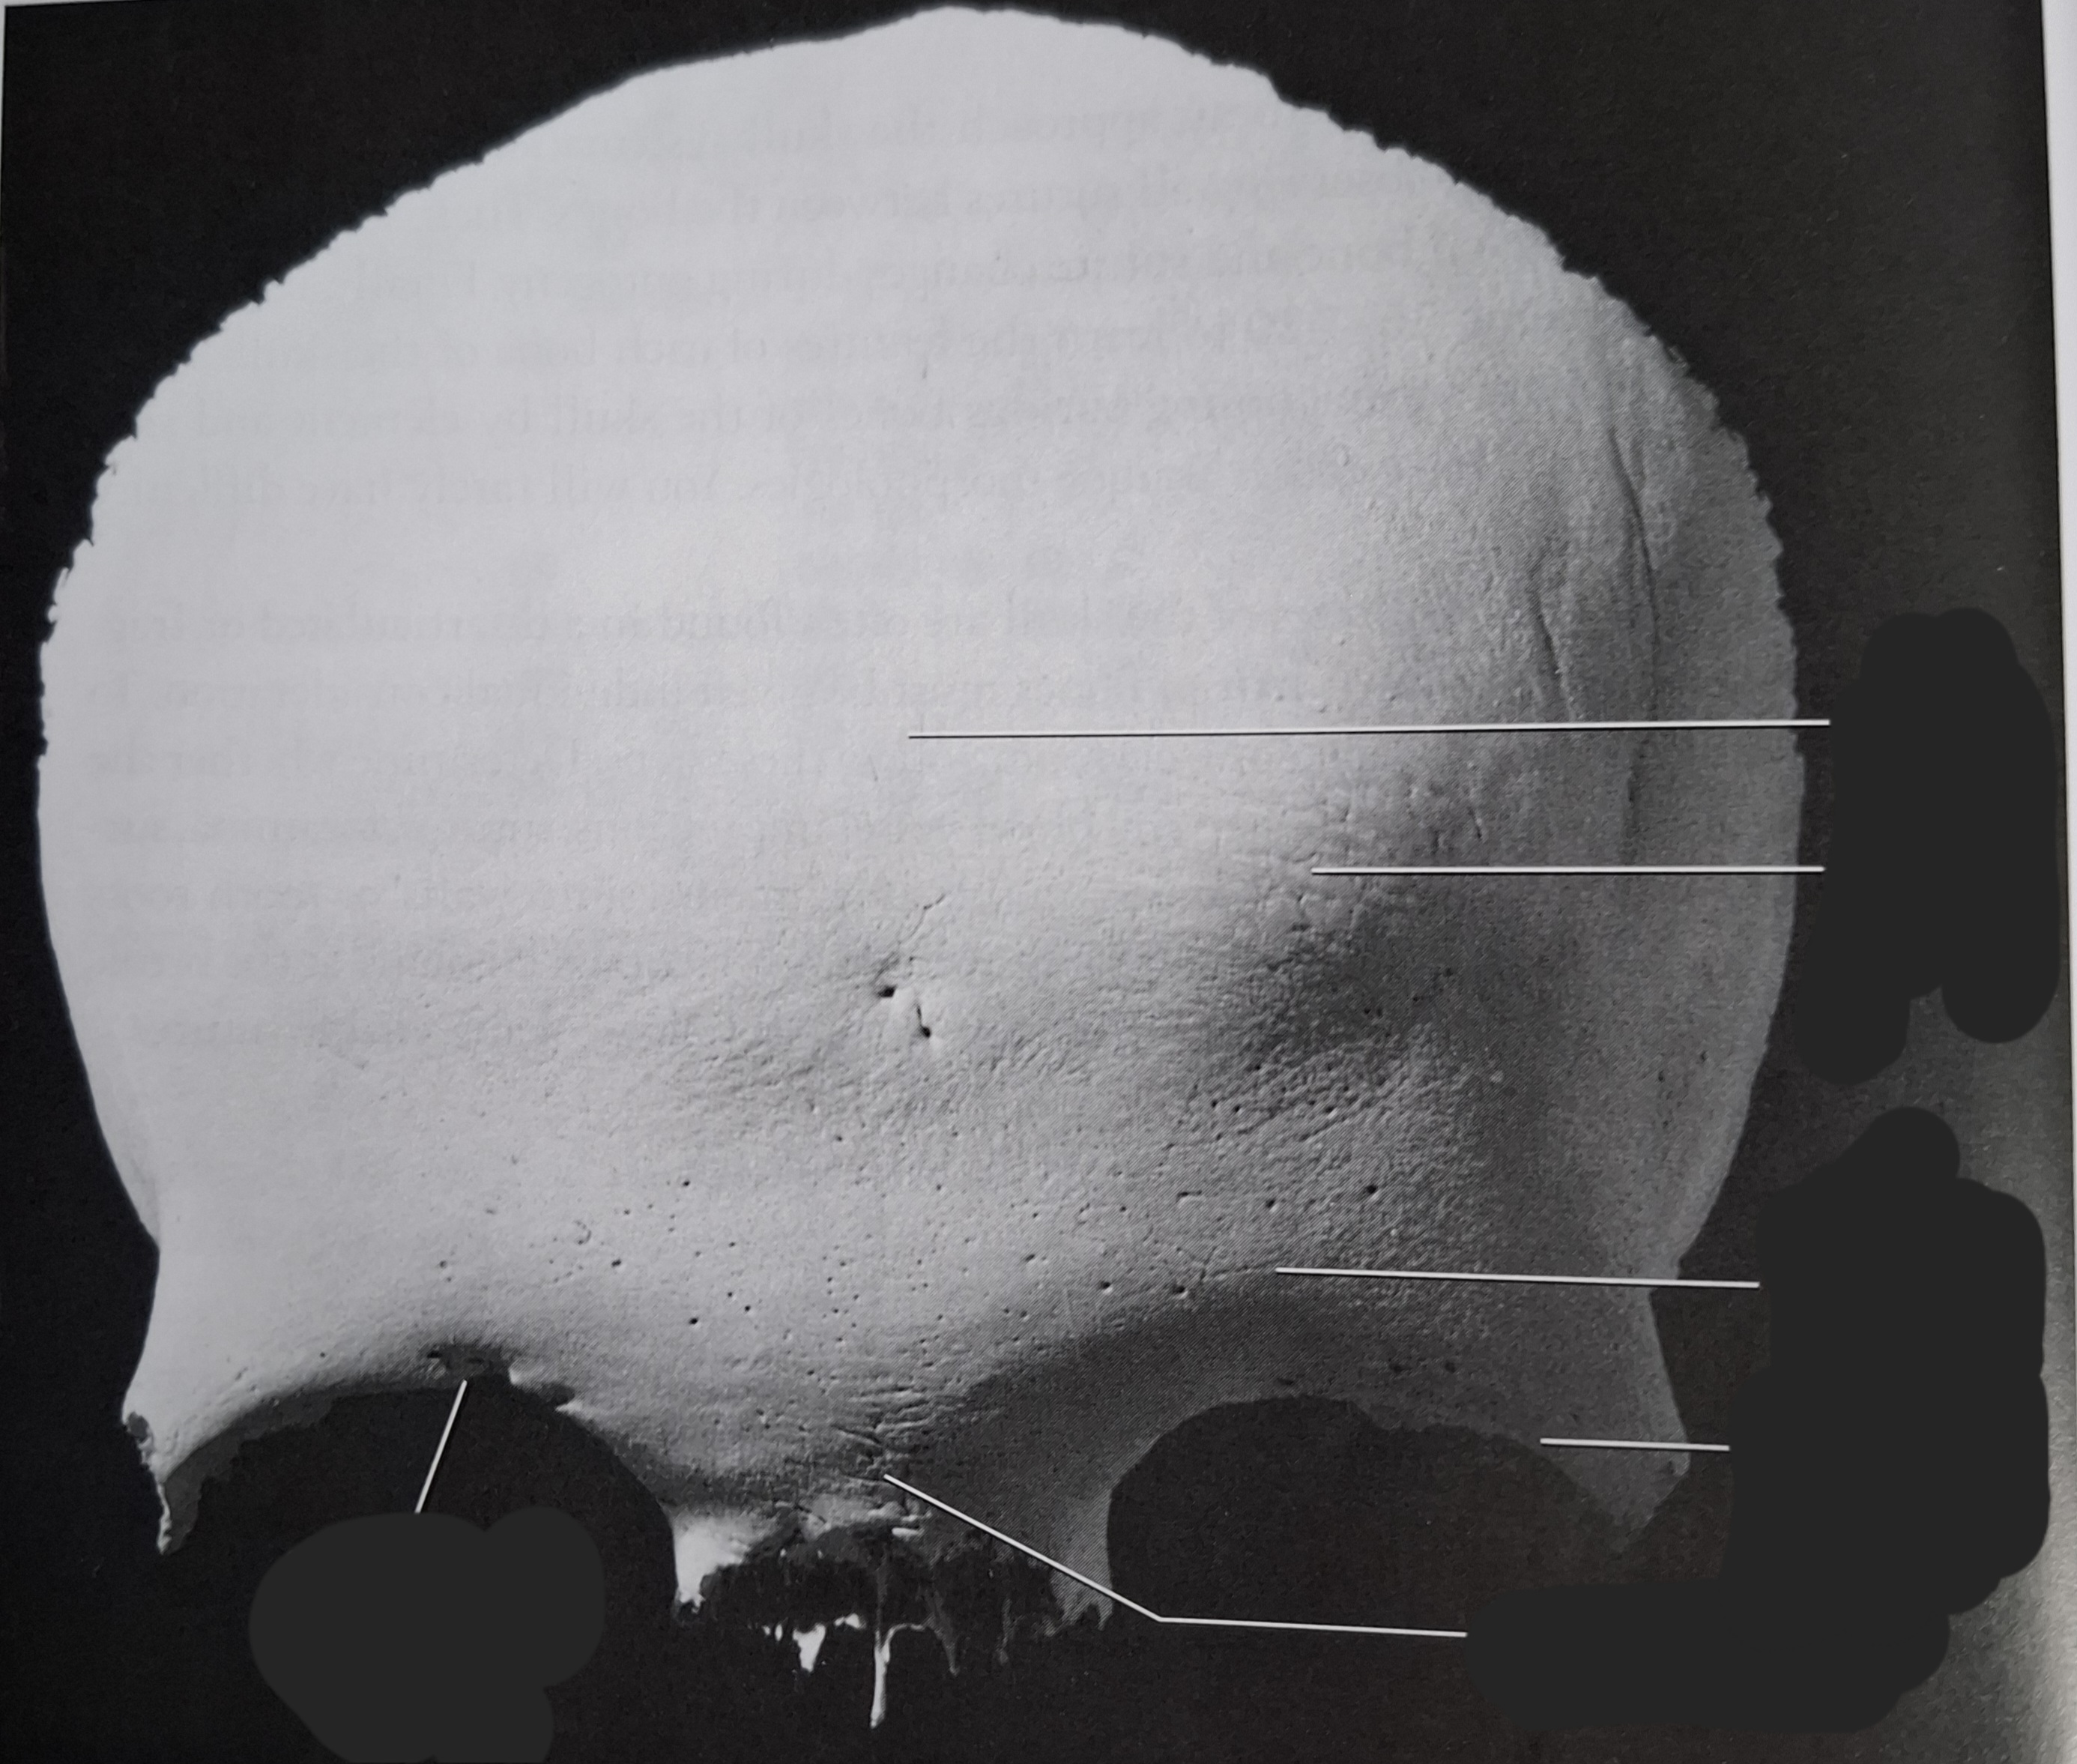

Occipital

Superior nuchal line

Inferior nuchal line

Foramen magnum

Occipital condyle

External occipital protuberance

Basilar part

Parietal

Superior temporal line

Inferior temporal line